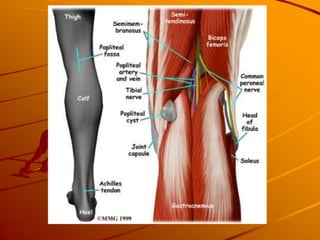

Baker’s Cyst

Outpouching of synovial fluid

Hx

– insidious onset of mild to moderate pain in posterior

aspect of knee

– Ruptured cyst may present like DVT – red swollen and

tender calf

PE – palpable fullness present medial aspect of

popliteal area

Imaging – US, CT may help if diagnosis unclear

Treatment

– Aspiration may cause temporary relief but recurrence

rate is high

– Surgery if pain persistent and intolerable